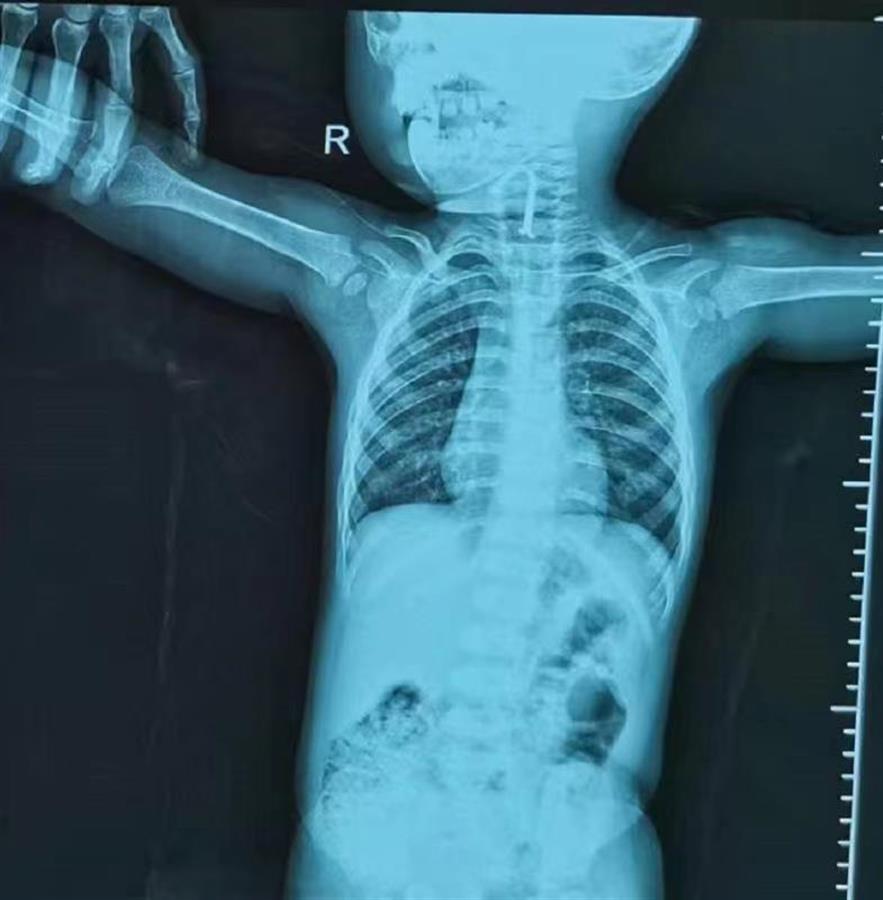

家住仙桃的小星年底要满2岁了。几天前,妈妈因事抽不开身,让五岁的姐姐带着弟弟小星玩。没多久,妈妈发现小星半张着嘴,口中不停流涎,还有干呕症状。妈妈察觉挂在客厅墙上的识字挂图掉在地上,挂钩只剩下了塑料部分,L型铁丝不见了。妈妈怀疑孩子把铁丝吃进去了,赶紧带他到当地医院就诊。检查发现,喉部有一个钩子样的金属异物,当地医院考虑到孩子小、手术风险高,将小星转诊到武汉儿童医院。

耳鼻咽喉科医生崔珑和崔华给小星手术,在全麻下用钳子取出一个长约3厘米的L型铁丝,整个过程不到一分钟。医生介绍,在食道镜下看到,挂钩没有完全滑入食道,弯曲处“挂”在会厌谷,另外一部分进入了食管,所幸食道并没有受损,会厌谷部位有轻微肿胀。目前孩子已经康复出院。

9月1日晚,武汉的1岁女孩笑笑(化名)趁家人不注意吞下异物后,一阵咳嗽和干呕,呼吸明显急促。武汉儿童医院耳鼻咽喉科医生急诊手术,用气管镜取出一个长约2厘米,宽7毫米LED发光二极管。